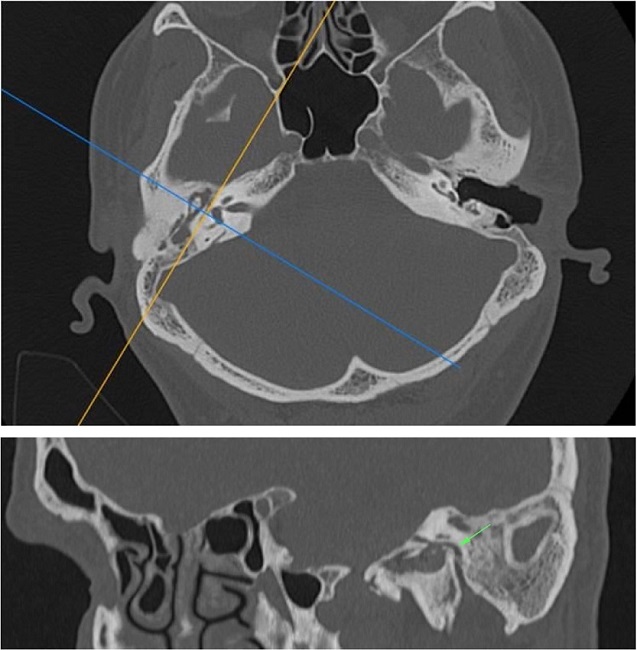

The Digital Imaging and Communications in Medicine (DICOM) files were retrieved from the Picture Archiving and Communication System (PACS) and transferred to the workstation for review; all measurements were done digitally by an experienced radiologist (A.T.S). All patients had preoperative temporal MDCT images taken. Temporal MDCT images with insufficient image quality were not included the study. Reformatted sagittal images were obtained from the thin-section axial MDCT images (Fig. 1A and B). Parallel lines from the tympanic and mastoid segments of the facial nerve were drawn in sagittal reformatted images as shown in the study of Hasaballah et al.8 Then, the angle at the second genu of the facial canal of all patients was measured (Fig. 2).